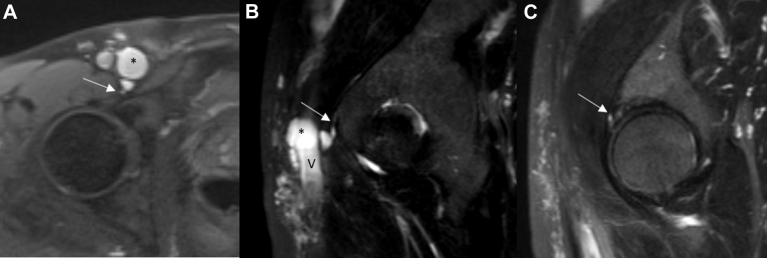

On examination, the patient had palpable pedal pulses and right lower extremity edema from the ankle to the thigh, without varicosities or skin changes. No palpable lymphadenopathy or masses were present in the groin. Anticoagulation was initiated, and thigh-high graduated compression stockings rated at 30 to 40 mm Hg were placed. A repeat ultrasound scan at 6 months demonstrated recanalization of the common femoral and saphenous veins with chronic post-thrombotic changes. Magnetic resonance venography demonstrated a 3-cm cyst anteromedial to the right common femoral vein that was compressing the lumen and another 1.2-cm cyst posterior to the vein and communicating to the hip joint (Figs 1 and 2). A labral tear was identified on the magnetic resonance venogram (Fig 1, C), which possibly contributed to formation of the adventitial cyst.

Fig 1.

T2-weighted magnetic resonance venogram images. A, Axial cut demonstrating the joint connection (arrow) to the cyst (asterisk). B, Sagittal cut demonstrating the joint connection (arrow), the main cyst (asterisk), and caudal common femoral vein (V). C, The origin of the labral tear (arrow).